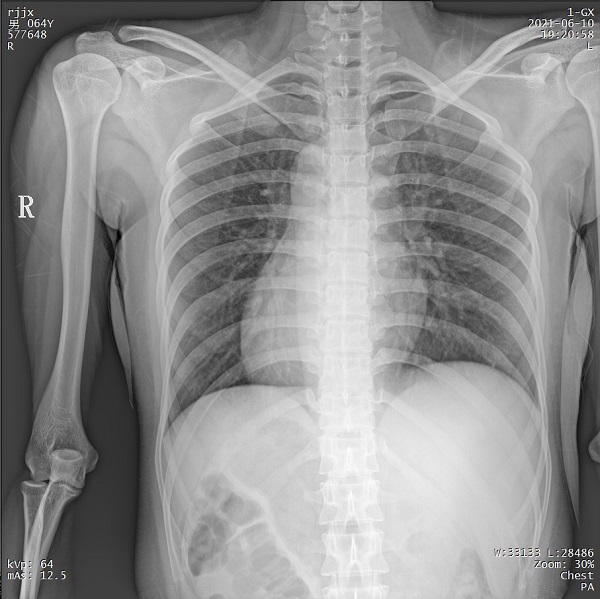

一、肥胖患者、組織較厚部位清晰成像

管電流大小與設(shè)備輸出X射線的能力相關(guān),管電流越大,設(shè)備輸出的射線量越充沛。PLX5500的最大管電流達到了710mA,輸出的射線能夠滿足各體型患者的拍攝需求,即便是體重達上百公斤的患者,也能夠獲得清晰的圖像。